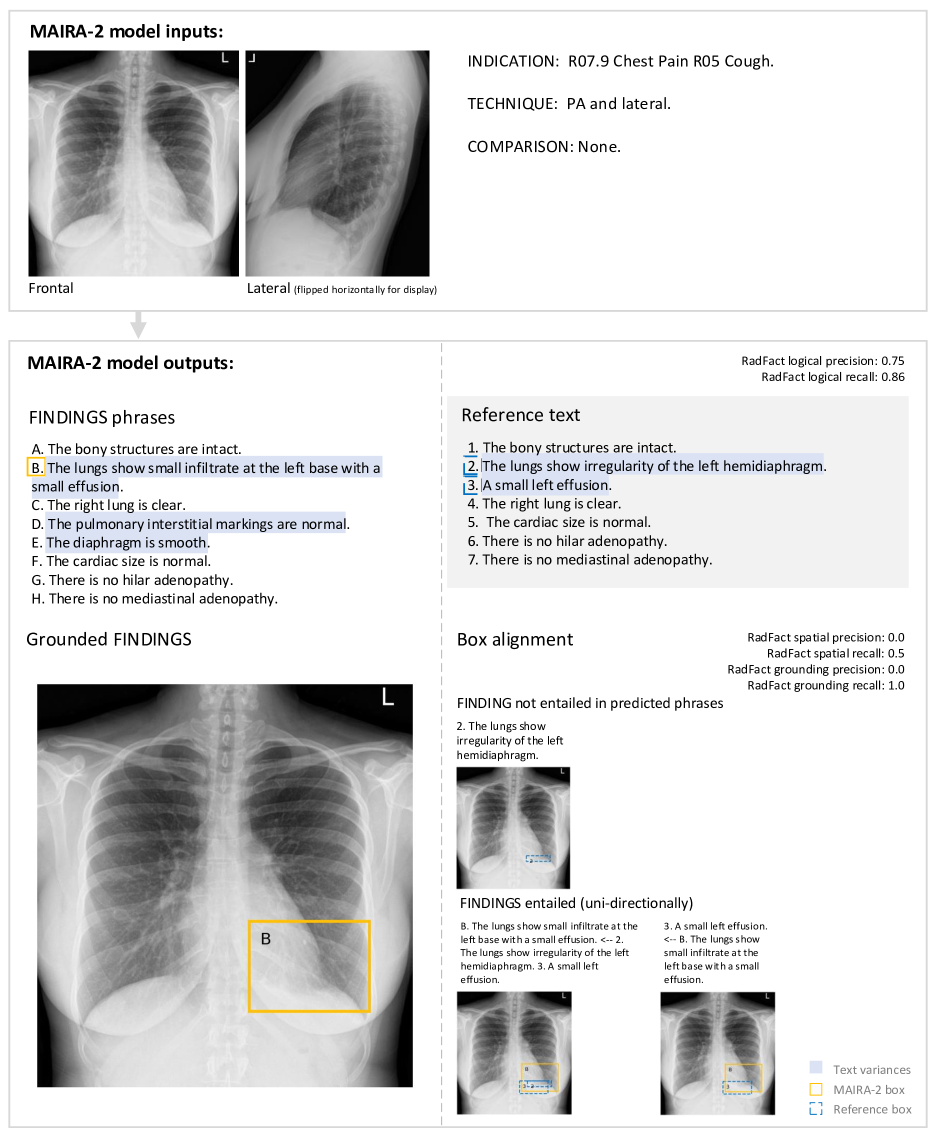

We define a grounded report as a list of sentences, (1) each associated with zero or more spatial image annotations and (2) describing at most a single finding from an image, as shown in Figure 1.

Spatial annotations indicate the region of the image pertaining to the described finding, and should be as specific as possible while containing the finding. Sentences describing non-findings (‘No pneumothorax’), regions of normality (‘Lungs are clear’), or abnormal findings without specific location (‘Diffuse disease’) do not require such annotations. In this work, we use bounding boxes as spatial annotations. Bounding boxes are commonly used to localise findings on CXRs (Nguyen et al., 2022; Wang et al., 2017; Boecking et al., 2022; Müller et al., 2024) and are easier to annotate than full segmentation masks.

The task is illustrated in Fig. 2. The generated and ground-truth reports are assumed to consist of lists of sentences, each describing a single finding. In a conventional findings-generation scenario, free-text reports can first be converted into this format as described in Sections 2.1 and A.2.

RadFact computes entailment in both directions, defining the following text-level metrics:

1.

RadFact logical precision: the fraction of generated sentences that are entailed by the ground-truth report. This measures how truthful the model generations are, as it penalises hallucinations.

2.

RadFact logical recall: the fraction of ground-truth sentences that are entailed by the generated report. This measures how complete the generated report is, as it penalises omissions.

Spatial and grounding entailment

We can then define a notion of spatial entailment based on pixel overlap: a region is spatially entailed by its evidence region(s) if at least a given fraction of its pixel mask is contained in the evidence pixel mask.666This pixel-precision threshold is set to 0.5 in our implementation with multiple boxes as the form of grounding, but could be adjusted, e.g., for finer-grained segmentation masks. This definition interprets a larger region as more specific than a smaller region contained within it, as the former makes stronger claims about where a finding is located. This provides for metrics on the text-and-grounding quality, analogously defining precision based on sentences from the generated report, and recall based on sentences from the ground-truth report:

RadFact grounding {precision, recall}: the fraction of logically entailed grounded sentences that are also spatially entailed. This tells us: which of the correctly described findings were also correctly grounded?

RadFact spatial {precision, recall}: the fraction of all grounded sentences that are logically and spatially entailed. This metric additionally penalises grounding incorrect sentences.

Figure 2 further illustrates how these metrics are defined. The fractions are calculated once in each direction: ‘precision’ scores describing the correctness of generated findings with respect to the ground-truth report, and conversely ‘recall’ scores indicating their completeness.